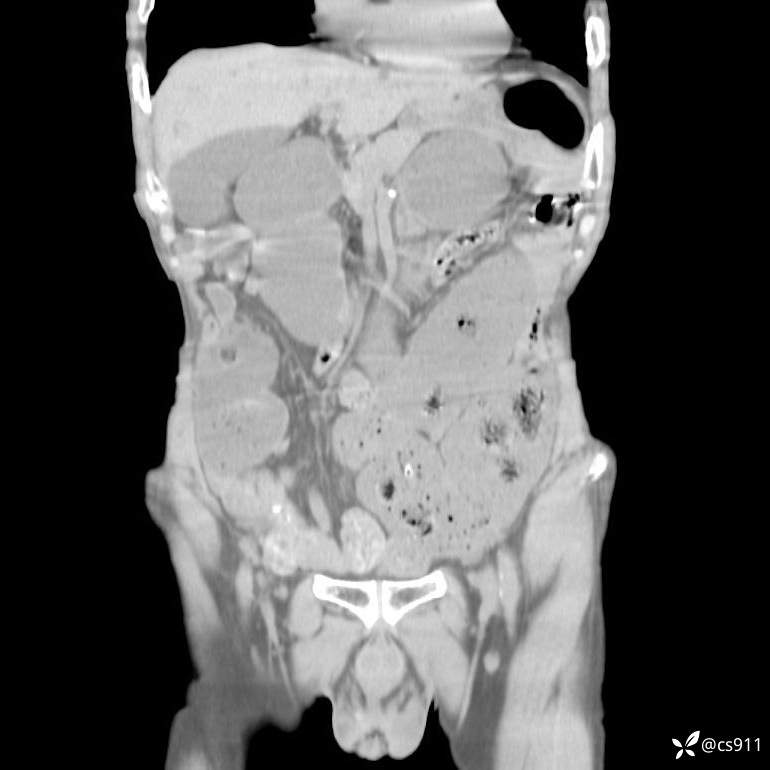

急腹症之急诊CT,原因?答案公布

男,77岁,腹痛、腹胀伴恶心呕吐1天。呕吐胃内容物,非喷射性呕吐,有咖啡色样胃内容物,诉有胃穿孔病史。查体:全腹平,下腹部压痛,全腹无反跳痛,叩诊呈浊音,移动性浊音阴性,肠鸣音减弱,1-2次/分。肛检:直肠未扪及明显肿物,可触及大量粪块。

T 36.6℃ P 80次/分 R 26次/分 BP 100/60mmHg

白细胞(WBC) H 14.55 10e9/L 4-10

中性粒细胞百分率(NEUT%) H 85.7 % 40-75

血淀粉酶(AMY) HH 1859 U/L 35-135

癌胚抗原(CEA) H 27.44 ng/ml 0-5

呕吐物 潜血试验 * 阳性 阴性

患者轮椅入室检查神志清楚, 能配合摆位和呼吸